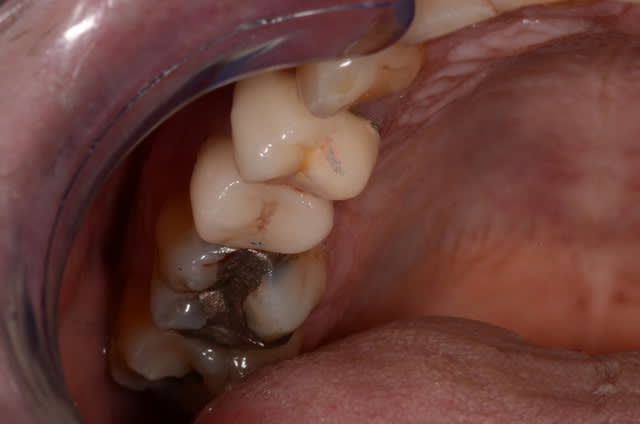

Inlay onlay de l'après-midi ^^ 47

j'attends son installation...tiens en attendant, ce matin en une séance fauteuil 46 et 47.

Vita markII

1h45 car le logiciel 3.85 a de fâcheuses tendances au bugs, et usinage plus long pour endocouronnes molaires , 550€/couronne.